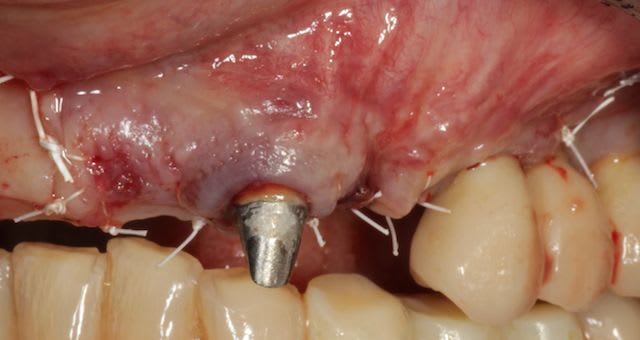

Grosse perte osseuse au niveau de la 23, ROG avec Bio-Oss et autogène dans un rapport 50/50, le tout recouvert pas une BIo-gide maintenu avec de pin's.

Désolé pour le retard, je vais essayé de répondre à tout le monde, mettre un implant et faire une ROG de façon predictible dans un cas comme ça c'est impossible, la photo pré-op c'est la dernière ( je ne sais pas pourquoi nonol m'a inversé l'ordre ), à noter que j'ai fait ce design d'incision car 24 et 25 sont des implants et je ne voulais justement pas me retrouver avec une récession.

J'ai utilisé du BIo-Oss et de l'autogène prélevé avec un scraper à la mandibule, le tout recouvert par une Bio-Gide maintenu par des pin's, suture avec du Gore Tex ( e-PTFE ) et du Cytoplast (PTFE )